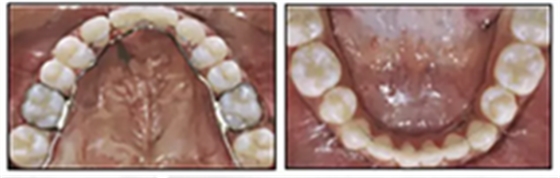

兩年半后,在上下牙弓上均實現(xiàn)了間隙關(guān)閉,并且使用0.017×0.025英寸的不銹鋼弓絲進(jìn)行咬合精細(xì)調(diào)整(圖8)。去除托槽后,上下頜采用舌側(cè)弓進(jìn)行保持(圖9)。

由于美觀和功能原因,要求恢復(fù)上頜尖牙和前磨牙,但患者希望推遲至成年后繼續(xù)這些治療。